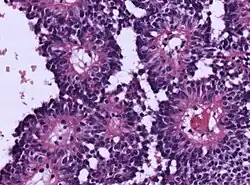

| Micrograph of an astroblastoma showing the characteristic nuclear pervivascular pseudorosette. H&E stain. | |